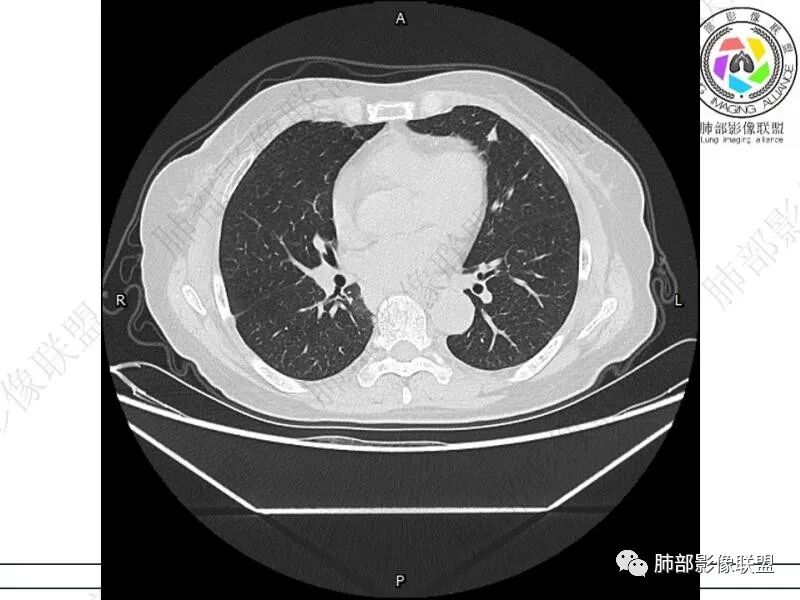

摘星空竹子:两肺胸膜下多发实性结节、磨玻璃影及实变影,短期复查病变有所进展,考虑感染性病变,隐球菌可能,患者有右半结肠癌手术史,转移不能除外。

简单:双肺及胸膜下多发小结节,双下肺胸膜下宽基底团块影,短期内病灶进展考虑炎性病变,隐球?患者ca术后,双肺小结节随诊除外转移

丽:双肺下叶胸膜下多发片状高密度影,边缘模糊不清,内可见支气管穿行,病变长轴平行于胸膜,考虑感染性病变,隐球菌

媛:肠癌术后,免疫力低下。两肺胸膜下结节及实变影,实变影长轴平行于胸膜,密度均匀,边界偏清,周围有晕征,短期复查进展,虽隐球菌荚膜抗原检测阴性,还是考虑隐球菌,鉴别OP

谢加平:结肠癌术后史,两肺胸膜下多发结节及斑块实变病灶,实边边界平直征(亚急性和慢性病变过程),双肺下叶后基底段胸膜下为甚,与胸膜平行特点,见支气管充气征,边缘模糊的GG0,首诊2022年11月18日肺部CT,与治疗11月28日对比,病灶未吸收,双肺下叶胸膜下病灶有侧向融合特点,综合分析符合炎性肉芽肿,隐球菌感染。

老年女性,结肠癌术后。两下肺胸膜下为主片状实变,右下肺短期复查融合且病灶长轴平行于胸膜,实变内可见支气管充气征,边缘磨玻璃晕,另两肺内胸膜下散在数枚小结节状、楔形实性灶。考虑感染性病变,隐球菌可能,鉴别肺转移。

2.影像特征:双肺胸膜下多发实性结节、磨玻璃影及实变影,胸膜下优势分布、晕征、胸膜下脂肪间隙存在,部分病灶边界平直征,有侧向融合趋势。